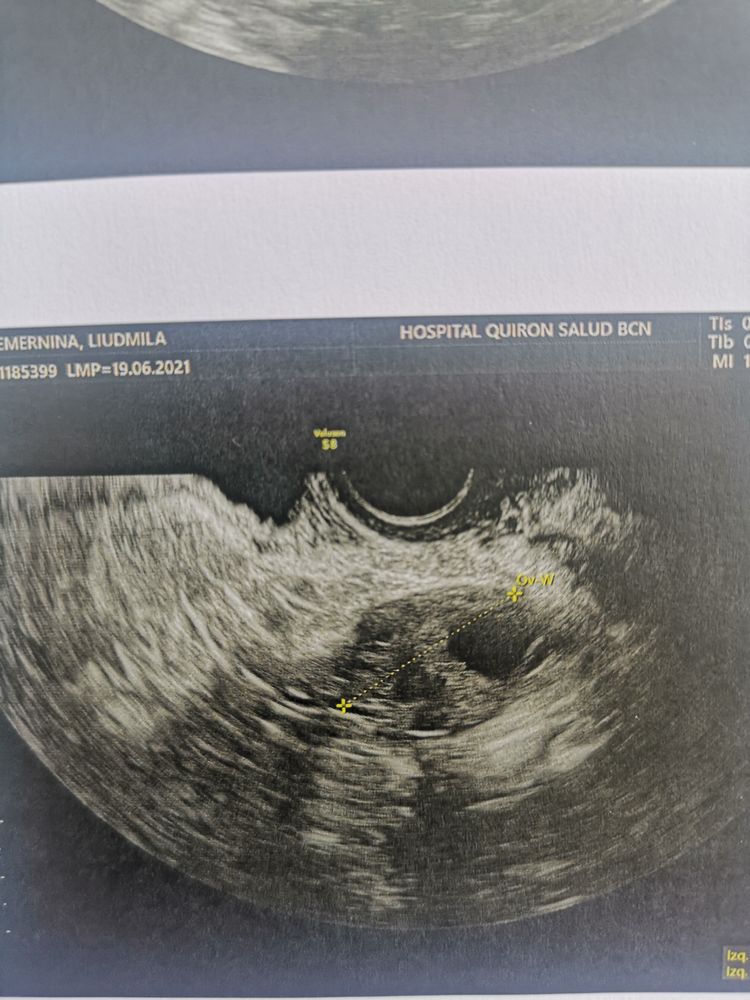

Девочки очень интересуют ваше мнение. Ситуация такая у меня ранней О не бывает, самая ранняя была за полтора года планирования на 12 дц. Обычно 14-16 дц. В пя раньше в ля позже. Сегодня 12 дц с 9 дц делаю тесты на О, тесты мне всегда отлично показывают О. Тесты никакие. Меряю бт и она растёт. По ощущениям О не было, выделения яб. Ради интереса пошла сегодня на узи и узист говорит О была и что есть жт 16*17, эндик 13 мм, но он у меня всегда отличный, сразу скажу этому узисту я не верю, так как он уже путал дф и жт. Брала запись к другому но почему то попала к этому. Ваше мнение это жт иди дф? Была О или ждать ее и делать дальше тесты? Я реально запуталась.